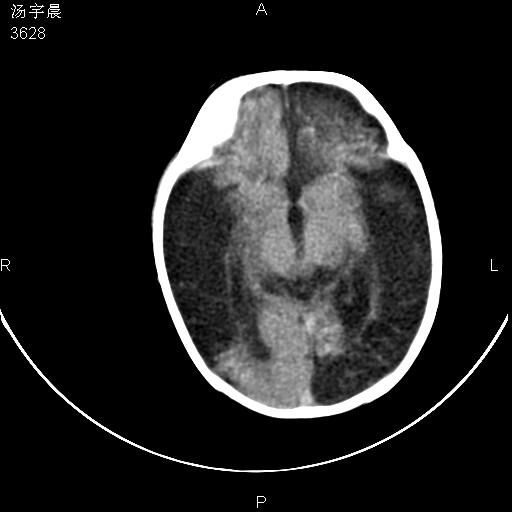

早产儿,现两月大,2月份在某医院诊断病毒性脑炎并治疗,mri报右颞部脑白质片状长t2信号,脑白质模糊。其他不详,现家属要求ct复查 。

双侧大脑半球大片状低密度,无明显占位表现, 符合病毒性脑炎。

小儿病毒性脑炎ct表现缺乏特异性,但其定位分布有一定特异性,单纯疱疹病毒性脑炎ct表现以颢叶病变为主,同时可累及其他脑区或伴出血,乙型脑炎表现为基底及丘脑的病变,流行性腮腺病毒性脑炎则ct表现可正常,故ct检查对病毒性脑炎的定性有重要的价值。 本例支持:病毒性脑炎的后遗改变!